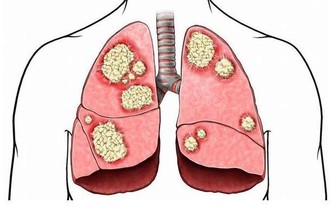

3、晚餐與腸癌晚餐若吃過飽,蛋白質食物無法完全被消化,在腸道細菌的作用下,產生有毒物質;加上活動量小及進入睡眠狀態中,使得腸壁蠕動慢,延長有毒物質停留在腸道內的時間,增加大腸癌發病率。